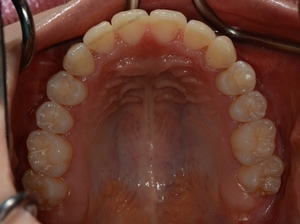

ガタガタとした歯並びや八重歯(叢生)CASE72